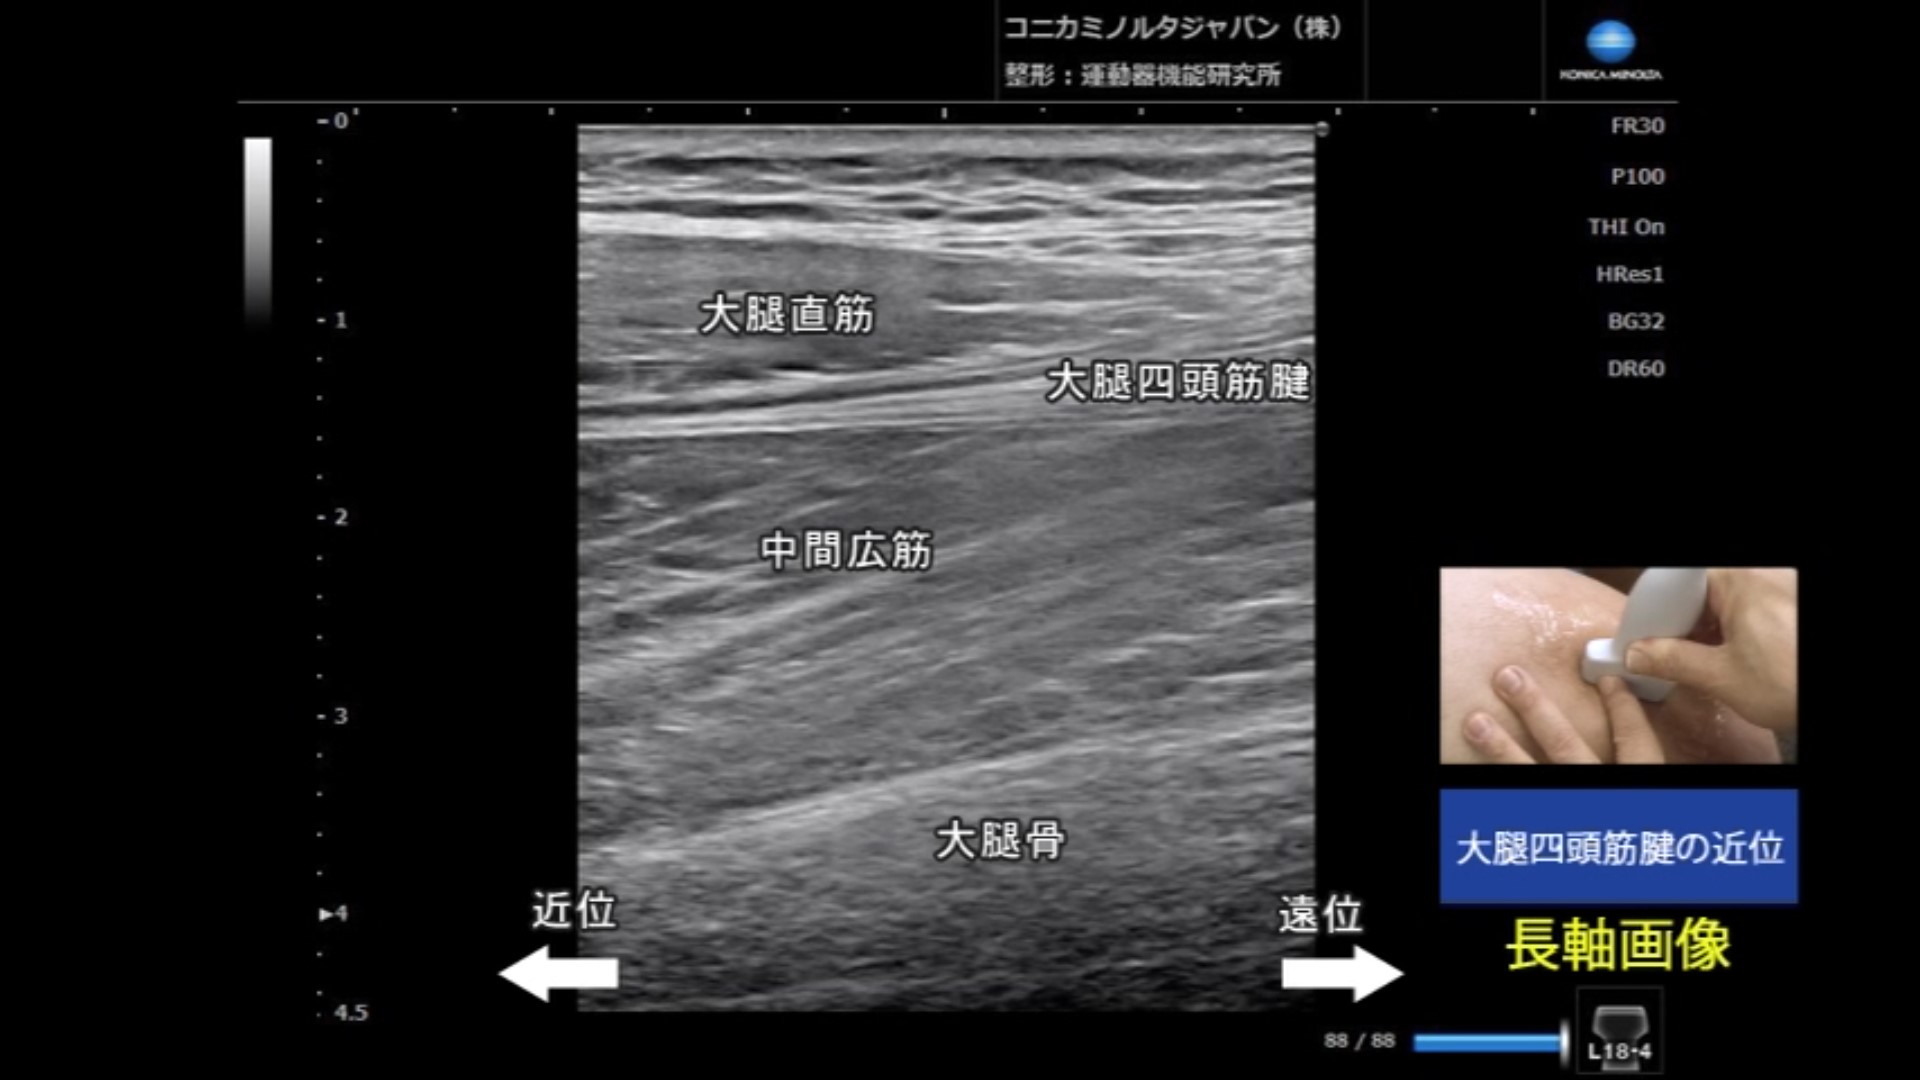

STEP(13) 大腿四頭筋

13分26秒